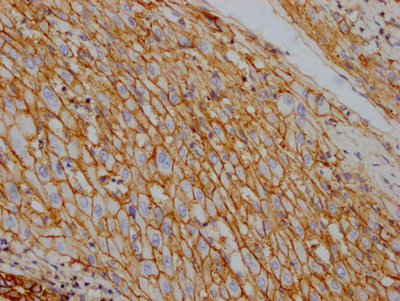

BackgroundThis is the catalytic component of the active enzyme, which catalyzes the hydrolysis of ATP coupled with the exchange of sodium and potassium ions across the plasma membrane. This action creates the electrochemical gradient of sodium and potassium ions, providing the energy for active transport of various nutrients.

DescriptionATP1A1 Recombinant Monoclonal Antibody [4C3]. Unconjugated. Raised in: HEK293F Cell.

ImmunogenA synthesized peptide derived from human Sodium Potassium ATPase

ApplicationELISA, IHC; Recommended dilution: IHC:1:50-1:200